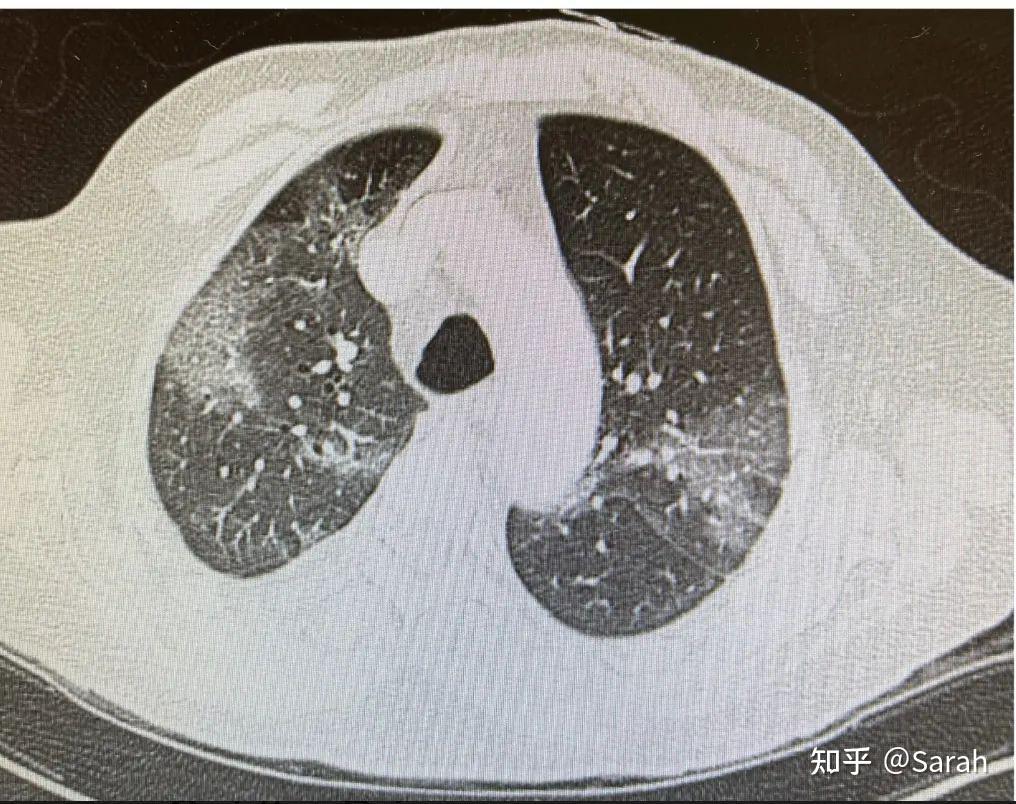

编前语乔人立医生是美国洛杉矶南加州大学医学院临床医学教授,2020年3月,他在洛杉矶疫情最黑暗的时候临危受命,一连10个月坐镇震央的洛杉矶总医院ICU,救治超过千名新冠危重症患者,把死亡率降低到全国平均值一半以下。不久前,他将自己救治经验在《呼吸界》直播间与大家分享,内容包括门诊过程、住院决定、危重症处理、激素应用、并发症评估等,受到极大关注,超过10万人次观看了本期直播,应呼吸同仁要求,我们将乔教授的发言整理成文,特此分享。今天我来讲讲「COVID-19急性期的管理」,用一个实际病例把目前指南之类的现有知识「捋」一遍。因为这三年的经历,非常了解大家现在的处境,我们都是同一战壕里的战友,面对各种困难,不只是不退缩,每天上班都相当于是在逆行,我们都是这样的无怨无悔。准备这个报告时,我想起2020年4月2日。当时作为ACCP国际事务总监,我牵头组织了由中国呼吸医师学会,美国胸科医师学会,以及中国驻洛杉矶总领事馆共同组织的连线会议。当时正是疫情刚开始在美国疯狂扩散的时候,四位身处武汉与上海的抗疫领军人物(王辰院士、瞿介明教授,曹彬教授、詹庆元教授),介绍了武汉的救治、理论等知识以及上海「压平曲线」的经验。当时好几万人听这个报告,包括CDC的人,实际上美国防疫模式的雏形就是根据这次报告做出来的。没想到三年以后,我们还在互相介绍着新冠经验。南加州大学下有三个附属医院,我平时主要的工作地点是凯克医学院(私立医院),平时原本不常去公立的洛杉矶总医院。新冠吃紧,洛杉矶总医院成了震央大本营,我被专门安排到总医院管ICU,因为哪里的医生顶不下来。从2020年3月底开始,将近11个月的时间都在总医院ICU里驻扎,当时的阵势大概和大家现在的经历差不多。总医院有8个ICU,每个ICU有16-20张床,所有ICU全都改成气流负压的新冠ICU。即使这样还是住不下、人满为患。这10个月期间,洛杉矶总医院的ICU里有2236个病例,其中我曾经经手的至少三分之一。从2021年,情况明显开始好转。2022年1月到现在,ICU一共才17个病例,其中还包括偶然新冠(因为其他原因进了ICU,新冠筛查是阳性)的情况,当时大家以为疫情就「过去了」,实际最近美国的新冠病例又开始增加了,但还没到吓人的地步。一、门诊过程这是一个真实的病例:68岁男性,既往史有高血压、糖尿病、前列腺肥大,更主要的还有急性淋巴性白血病,经过化疗后缓解,2022年4月做了骨髓移植。2022年11月时,他打来电话,自诉近两天嗓子疼、干咳、痰很少,胃口和一般活动能力都和基线差不多。体温38.7摄氏度,血氧饱和度97%,COVID-19检测呈阳性。作为医生,接到这位患者的电话,你应该想到什么?该怎么办?这里牵涉着处理门诊患者的基本原则。有4个选择,1、吃降体温的药,2、开Paxlovid回家服用;3、紧急送到急诊室抽血、做胸片;4、收住院。哪个是大家的选择?患者如果年龄符合、危险因素符合、一般情况还好的话,回家服用Paxlovid应该是指南推荐的标准选择。但这是一位骨髓移植患者,血液科做骨髓移植的医生对他,就像我们对待做过肺移植的患者一样加倍小心,坚持把这位患者收到医院里来服药。我们做各种选择的根据是什么?现有指南列出来了6条:第一条:要评估一下病情轻重、有多急。需要关注的症状是「气短」,或「氧饱和度」。发烧、嗓子疼,全身痛都是很难受的症状,但却并不足以作为判断病情严重程度的指标。第二条:要验证一下患者的症状是不是因新冠引起的。现在在大多数人都新冠阳性的情况下,基本上就需要考虑是新冠感染。但仍然要想想,患者会不会合并了细菌感染、会不会感染了肺结核?或是链球菌咽喉炎?至少要排除一些可能。第三条:要判断下这位患者进展成危重症的危险因素,如并发症、年龄、是否肥胖等。第四条:要不要抽血看看是否有炎症风暴?拍张胸片?在门诊上,患者如果一般情况还好,现在的指南建议是「用不着」。一方面,检查结果不会改变治疗方案;另一方面,反而给患者增加了活动范围与接触人数,无故使感染播散的几率增大。第五条:要不要把这位患者收住院?还是在门诊服药就可以了?这里面含有非医学因素,需要考虑他的家庭环境的安全性,有没有人照顾他?如果病情加重,有没有人会把他送到医院来?在同样病情下,可以根据这点来决定患者是否应该直接收入院。(前文提到的患者的主治医就是因为这条原因将他收治入院了,住院的主要目的是「监测」,而不是进行输液等「治疗」)。第六条:目前情况下,来就诊的患者都有点「人心惶惶」,一定要做一些咨询,以安其心。这6条是门诊最主要需要重视的,具体怎么做大家都很清楚了。虽然目前新冠的整个病理生理还不完全清楚,但根据现有的临床证据,新冠的处理大致可以分成早期和晚期。这样区分的意义在哪里?早期一般是在5天,最多10天以内,这时「病毒的感染和复制」是主要需针对的问题。过了这段时间后,炎性反应就开始出现了,包括炎症因子风暴、包括造成的组织损伤,这些共同导致的一个核心环节就是「会不会形成缺氧」。缺氧并不是因为患者呼吸到的氧少了,而是因为肺损伤损伤了血气交换屏障,影响氧吸收。这里的基本概念是,缺氧反映的是炎症损伤对肺的损伤程度。这是处理急性新冠的一个关键点。对于早期新冠的处理,要考虑的是要不要给予抗病毒药,有什么药物可供选择?1、Paxlovid;2、瑞德西韦;3、高滴度的恢复期血浆。在这种情况下不要用激素,因为激素不是抗病毒的药,而是抑制免疫的药。此时使用反而有可能使病毒的侵犯更加严重。病情严重程度的评估评估主要依据年龄、危险因素,和病情严重程度这三条。每条都有切实的客观依据。无症状患者就不用讲了。什么是轻度?关键是没有证据提示「缺氧」,例如没有喘不上气、没有活动性呼吸困难。什么是中度?无论是从检查、分析、影像上,只要发现患者已经有了「下呼吸道感染」,不单纯是上呼吸道感染就叫中度了。这时还没出现缺氧。什么是重度?就是已经开始出现缺氧时。想给大家提示一下,缺氧不等于「患者不行了」、至少不至于立刻致命,其意义是表明患者体内的所有储备已经用尽,只有稍微有点变化,就会进入到危重症状态。所以发现重症时就应该住院,因为到这种情况时,病情很可能在几分钟内就发生不可预期的改变。什么是危重症?首先是ARDS规模的缺氧。第二,血流动力学已经不稳定,缺氧损伤的第一步生理变化就是血压降低。此外,各种过度的炎症反应、血栓形成等等都属于危重症。还有基础病加重,比如慢阻肺病加重、哮喘加重、糖尿病发展为酮症酸中毒等等。再次强调,对病情的判断,每一点都要依据客观证据,而不能仅凭我们的主观印象。二、住院决定回到这位患者。他被收住院了、吃了Paxlovid,很快好转,5天就回家了。可是一个月以后,他直接来到诊所。这时,高烧39.9摄氏度、氧饱和度在呼吸补氧下89%,新冠仍然是阳性……这时应该考虑什么?鉴别诊断是什么?你又应该做什么?这里大家一定要学会清楚的区分两个概念。一个是「rebound」,反弹或病情反复,它的本质就是「上一次感染没好」,仍然是同一个病毒。反弹一般都应该在第一次发病10天之内出现,而且症状往往比较轻。如果判断是病情反弹,那不需要再吃药了,但因为还有传染性的,仍然应该隔离。服用Paxlovid的患者反弹很常见。但如果认为这是「二次感染」,情况就不一样了,二次感染就意味着是一个新的感染,就需要按照新的病例处理。在这里稍微讲讲基础的科研数据,日本一项研究发表在《nature》(自然)杂志上,观察新冠感染后,血清里的免疫球蛋白的浓度变化。大家知道一般情况下,感染初期生出的抗体应该是IgM,大致持续三个月左右消失,然后IgG开始逐渐上升,但新冠患者的血清免疫球蛋白浓度曲线不完全这样,IgM和IgG都在5~7天就开始上升,维持到10天,10天以后才达到真正抗体浓度平台期。相对我们的传统认知而言,稍有意外的是IgG也在几天内就开始上升了,在7天到10天达到平台期。根据这一数据,在7天之内,要考虑反复;7天、尤其是10天以后,就应该考虑是第二次(新的)感染了,因为抗体已经对前一个病毒形成了足够浓度。我们系里有一位fellow做科研,一直在测系里每一个人的抗体反应曲线。我自己在没打疫苗时,IgG、IgM都是阴性,接种了辉瑞的疫苗(21天两针),接种第二针后才7天,IgG就很明显了,可是IgM一直不明显。重要的是,打完第二针6个月以后,我原有的IgG没有了。很多人是继续有的,但我们系里三个华裔的IgG全都消失了,不知道这是不是受遗传、种族的因素影响。但这并不等于免疫力没有了,因为我们的免疫力存储在记忆细胞里。这个检测是粗糙的,没显示出来可能只是因为没达到它的阈值。后来,接种了第一剂Booster Shot加强针6个月后,IgG没有再消失,反而更加强了。可见加强针确实有「加强」的作用,一定要鼓励患者去打疫苗。三、危重症处理再回到这个病例,这位患者收到医院了,做体检:体温39.7摄氏度,脉搏109,血压107/47mmHg(虽然还正常,但这是位高血压病人,对他而言偏低了)。呼吸也加速了,80%的吸入氧才勉强将氧饱和度维持在94%。计算出的氧分压和吸入氧浓度的比值(PF值)才75(比值在300以下时就开始考虑是ARDS),是很严重的缺氧了。患者此时也明显开始呼吸困难、嘴唇和手指出现紫绀。血气分析,pH7.35,二氧化碳分压32mmHg,这时有点过度通气了。氧分压是67mmHg(80%吸入氧的情况下),计算下来,PF值是75。这时立刻做了CT(图1)。大家都应该很熟悉这样的图像,我再强调一下,新冠的CT图像特征是毛玻璃影,但毛玻璃影本身不是特征,关键它是片状的、外周分布型的毛玻璃。我选的这个截面偏高,因为要和后面的一张CT来做比较,实际患者的毛玻璃影从肺尖一直到肺底全都有,在肺底部更重一些。

图1:COVID-19 CT影像血检查,D-二聚体3.66(正常值小于1),纤维蛋白原244,转铁蛋白1711(新冠中转铁蛋白作为一个炎性因子的指标,而不一定真的代表铁浓度)。患者其他的指标也都很高、高于正常值几倍。心肌酶0.237,偏高,我们认为这是缺氧导致的,并没做什么干预(大家记住这个数值,稍后分析病例下一步时会用到)。白细胞4.58,血小板19,血红蛋白7.5,这是不是因为新冠的影响呢?通常情况下,我们需要考虑是不是新冠影响了骨髓,但这位患者是一位白血病患者、骨髓移植术后患者,他的骨髓还没有完全达到正常人的水平,基线的血小板就在40以下,血红蛋白一直在8克左右。真正和新冠比较有特异性关系的是「淋巴细胞比例偏低」,武汉疫情时,各种数据就提出,淋巴细胞偏低对判断预后有意义。另外,患者有轻微的转氨酶增高,乳酸5.3,有点升高,这纯粹是因为缺氧了。做治疗决定时要保持基本概念清楚。这位患者显然是属于危重情况,所以才收进医院,收住ICU的。此时,治疗的主要目标必须瞄准抑制炎性反应,用地塞米松或甲强龙。指南上说,可以用瑞德西韦,但一定要在免疫抑制的基础上才能用。新出来的还有两个免疫调节药可以可以考虑,JAK抑制剂和白介素6抑制剂。指南推荐危重症患者用地塞米松可以加用JAK抑制剂,或是白介素6抑制剂。因为这两个抑制剂价格昂贵、供应量偏小。如果无法获得,就单纯用地塞米松。这是指南特别强调的,而不能反过来,不能不用地塞米松而只有这两个抑制剂。实际上地塞米松完全可以达到这两个药的作用,费用还要更加便宜。指南上还说,可以在免疫调节基础上可以加用瑞德西韦,因为瑞德西韦是针对病毒的抗病毒药,一定要在患者存在高危险因子时考虑使用,而且不要单独使用。现在我们都是循证医学,clinical trial的结果是什么就是什么,没有回旋余地。实际个人经验里瑞德西韦疗效微乎其微。还有问题需要讨论,这位患者的D-二聚体比正常值高了差不多4倍,要不要用肝素呢?新冠抗凝的观念确实明显有变化。在疫情初期时,基本所有指南都是依据D-二聚体的浓度来决定肝素抗凝到什么程度,如果D-二聚体已经4倍高于正常值,当时推荐全剂量抗凝。现在不做推荐了,只推荐预防剂量的肝素。如果患者有其他胃肠道出血等等禁忌症的话则禁用,效果和害处的「益害比」已经有所变化。甚至指南专门提到,如果患者转入ICU前已经使用了治疗剂量肝素,就要考虑停掉它,除非有深静脉血栓等等指征。这位患者收到ICU后,我们使用的是甲强龙、高流量鼻管吸氧、俯卧位、瑞德西韦。俯卧位是一直保持到现在的、认为对患者有好处的治疗手段。四、详解激素应用我们细致讨论下激素的选择。激素是个老药,尽管在新冠中启为新用,依据仍然是激素的药理。因此,给患者用激素时,不应该死板教条,自己首先要很清楚激素的药理作用、生理作用。我们在此把激素的基础知识先过一遍。静脉点滴可用的激素有三种,氢化可的松、甲强龙、地塞米松。作为药物使用和作为激素使用的区别在哪里?如果它作为激素使用,作用是通过类固醇,和受体结合后再进入细胞核,进而影响细胞的代谢。而一旦作为药物使用,就比生理浓度高出几十倍,这时所有的受体都已经被饱和了。因此,虽然仍然称为「激素」,医师应该非常清楚,其药理是通过这些分子直接和细胞膜结合起到的药理作用,和「激素」作用已经基本无关。三个ICU常用激素之间有所区别。首先,药物的强度不一样,按照大致的比例换算起来,以氢化可的松作为1的话,地塞米松是25倍,甲强龙是5倍;如果需要用100毫克的氢化可的松,那地塞米松应该才用4毫克、甲强龙用20毫克左右。还有一点更重要、和我们稍后的讨论非常有关的就是这些激素在药理「半衰期」。虽然生物半衰期可能很长,在危重情况的疗效要保持持续的血清浓度,使用氢化可的松需要一天三次、甲强龙一天三次、而地塞米松应该一天四次。除了这些区别,各自的首选适应症也有不同。如果你是一位内分泌科大夫,患者出现肾上腺皮质功能不全、血压很低,首选用什么药?大家最先想到的肯定都是氢化可的松。第二,如果患者出现创伤性的损伤,如脑损伤造成脑水肿、如耳鼻喉科的气管操作后的声门水肿。这时水肿虽然要属于炎症表现,但这些炎症不主要是细胞因子引起的,而是因为局部机械性损伤。对于神经外科医生而言,处理脑水肿该用哪个激素?大概人人都会选择用地塞米松。对于耳鼻喉科医生而言,患者声门水肿时,大家往往也会选择地塞米松。为什么会这样?因为这三种激素和细胞膜结合的亲密度不一样,所以造成的细胞反应有区别。而我们作为呼吸科的医生,处理的肺内炎症反应多半都是细胞因子引起的,如过敏性肺炎、如NSIP,如肺移植急性排异、如狼疮肺炎,如类结节病,这些情况下要用激素,应该选什么呢?呼吸的教科书上一律指向甲强龙,而不是氢化可的松和地塞米松。为什么要做这种讨论?现在面对新冠时该怎样选择激素用药?我们自己做过试验。激素的争论从SARS时就开始,却惜无定论。我曾经强力建议逆行武汉的同事一定抓紧测试激素效果,甚至写过专文,却仍然未得实施。所以我一接管ICU第一件事就开始测试激素效果。本来是有目的的想分组做试验,后来一看没法弄。一来,没有时间提交伦理批准进行正式试验。二来没有别人相信「激素对新冠有用」。这样,就顺其自然的形成了分组。这项试验的主力是住院医和PCCM fellow,当然主意与设计是我拿。我们选的是甲强龙(甲强龙本身就是常规的临床用药,所以用了也没有人来找麻烦),因为我们觉得新冠的炎症因子风暴介导肺里的各种炎症细胞所致损伤应该是病理变化的核心。从2020年3月就开始坚持固定的激素方案。大概5月时,RECOVERY试验结果发表,证明地塞米松能降低新冠死亡率,但改善后的死亡率仍然超过20%。回想下我们对地塞米松的了解,它的强度虽然可以换算,但还有半衰期的问题、亲和力的问题,但是,既然现在要强力压制的是肺内的炎症因子风暴,地塞米松不应该是首选药,估计当时设计实验的不是呼吸科医生。不管怎么说,这个报告出来后,其他医生立刻全都给患者用上地塞米松了。反而有个好处,使得我们这项试验有了三组相对「齐头并进」的数据可以进行比较。看看28天死亡率,较之无激素的35%,甲强龙组降低到15%,而且较之地塞米松组有进一步改善。(图2)